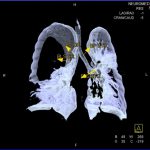

În cazul traumatismelor cranio-cerebrale:

- Evaluarea deplasării liniei mediane

- Evaluarea cisternelor perimezencefalice

- Diagnosticul edemului cerebral, a contuziei cerebrale, a leziunilor axonale difuze edematoase/hemoragice, a dilacerării cerebrale, a hematomului intraparenchimatos posttraumatic, a hematoamelor subdurale/extradurale (acute, subacute, cronice), a hemoragiei intraventriculare, a hemoragiei subarahnoidiene

- Diagnosticul traumatismelor de bază de craniu